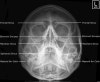

6. Adult Sinuses - Occipito Mental OM (Waters)